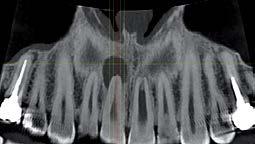

L’innovazione e la sicurezza sono due dei valori perseguiti dallo Studio Braconi a Terni, un punto di riferimento nell’ambito della radiologia 3D ortopedica grazie alla presenza del macchinario Newton 5G XL: si tratta dell’unico apparecchio nel Centro Italia che permette di eseguire una perfetta diagnostica per immagini in ortopedia e per la cervicale, oltre per le piccole articolazioni come seni paranasali, orecchie, colonna cervicale, gomito, polso, mano, ginocchio, caviglia e piede.

Nell’ambito della radiologia 3D ortopedica, il centro diagnostico utilizza il nuovissimo macchinario NewTom 5G XL, in grado di individuare con la massima precisione la presenza di fratture o lussazioni delle articolazioni, controllare la corretta guarigione di una frattura, valutare una lesione o una ferita causata da infezione, artrite o crescita anormale dell’osso.

Il tutto mediante una semplice e veloce scansione, grazie alla quale si otterranno diverse immagini in 3D ad altissima risoluzione e, per ottenere immagini ancora più nitide mediante un bassissimo dosaggio di radiazioni, gli esperti si avvalgono dell’innovazione racchiusa nella tecnologia Cone Beam.

Un altro valore aggiunto che rende la radiologia 3D ortopedica uno strumento fondamentale nell’ambito della diagnostica per immagini attuale è la bassissima dose di radiazioni emesse: infatti, la tecnologia CBCT garantisce una dose fino a 10 volte inferiore rispetto al MSCT.